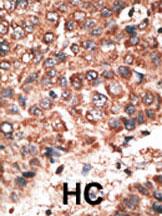

Formalin-fixed and paraffin-embedded human cancer tissue reacted with the primary antibody, which was peroxidase-conjugated to the secondary antibody, followed by DAB staining. This data demonstrates the use of this antibody for immunohistochemistry; clinical relevance has not been evaluated. BC = breast carcinoma; HC = hepatocarcinoma. |